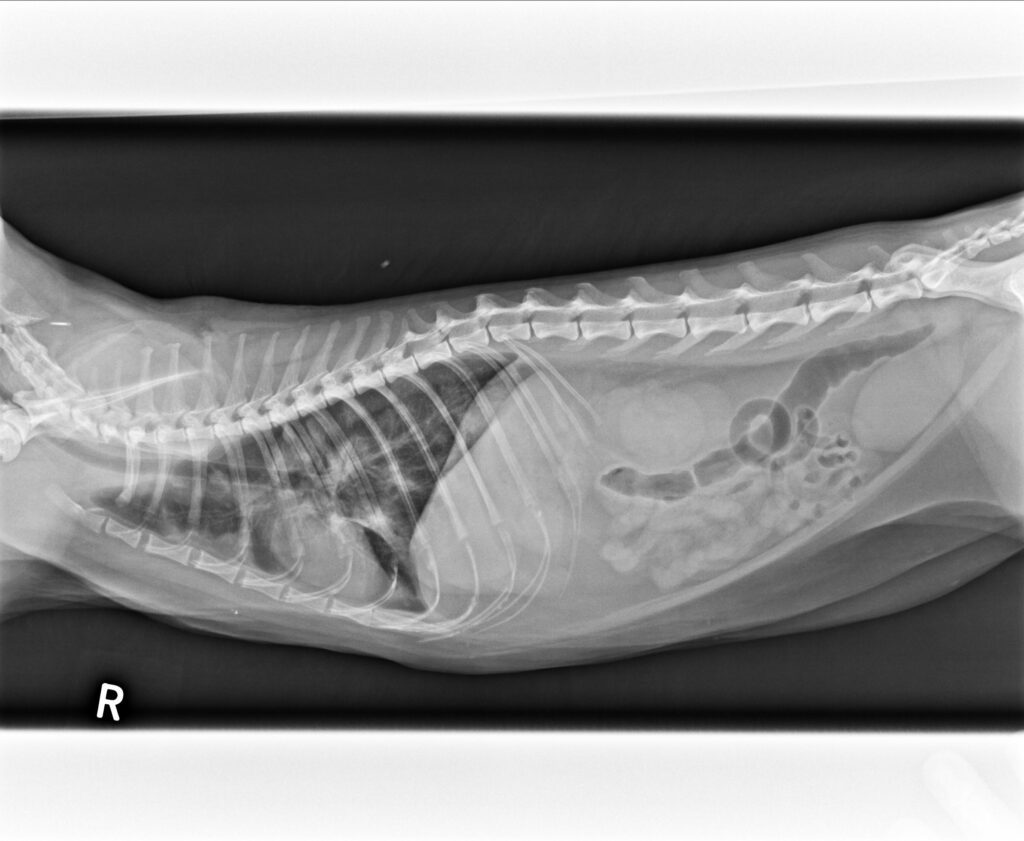

2023/5/17, 六天後橘貓的喘促幾乎改善,並且辦理出院,由愛心人士接手後續照顧。 今天其中一位愛媽也帶她家的貓來看,並聊到橘貓在她家前面繼續閒晃、巡邏地盤而感到欣慰;在這裡橘大夫由衷感謝這位愛媽的信任,醫師得到信任才敢盡全力來挽救生命,醫病關係的良好才能夠得到今晚美好的回憶,大家晚安。

胸腔X光1-3張見到瀰漫性結節團塊浸潤